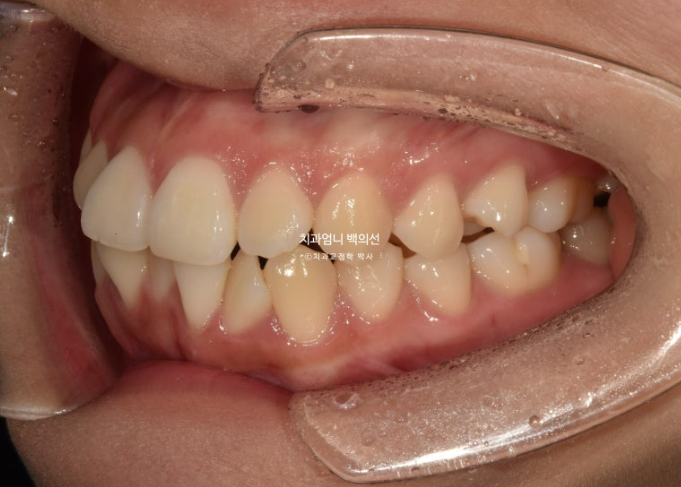

2023년 12월 앞니 부분교정을 원해서 내원한 분 입니다.

파란 화살표에 작은어금니 덧니도 보입니다.

아래 앞니가 많이 삐뚤 합니다.

어금니 교합이 그리 좋은 편은 아니었지만 환자분은 씹는데 불편함을 못 느끼는 상태였고 앞니 배열만 원하셨습니다.

기간과 비용, 환자분의 상황 모든 것을 고려하여 일부 포기하고 앞니 부분교정에 들어갔습니다.